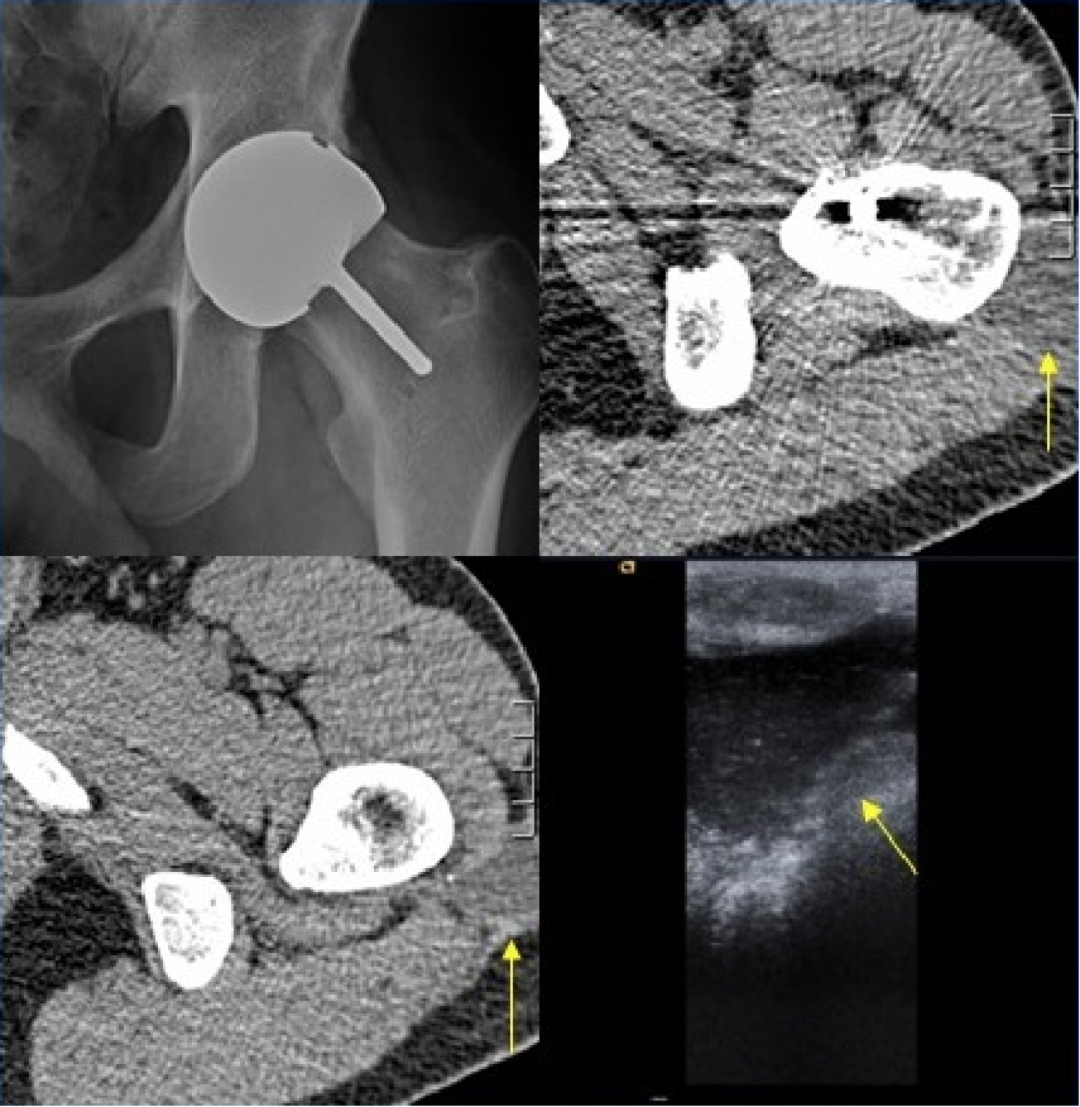

4.骨溶解:

发生率 5%~9%,与透亮线不同,地图样透亮区是由假体相关的骨水泥、金属或聚乙烯颗粒诱导的组织炎症反应所致(颗粒病)。

右侧髋臼及耻骨支骨质溶解吸收,关节周围团块状软组织肿块,围绕股骨头及股骨颈

5. Metal-on-metal(MOM)disease:

假性滑囊,是金属对金属髋关节置换的组织反应;表现为髋关节假体周围的滑囊。最常见的部位是:髋臼上缘、大粗隆和小粗隆。

人工髋关节置换术。假体周围囊性肿块(箭头)